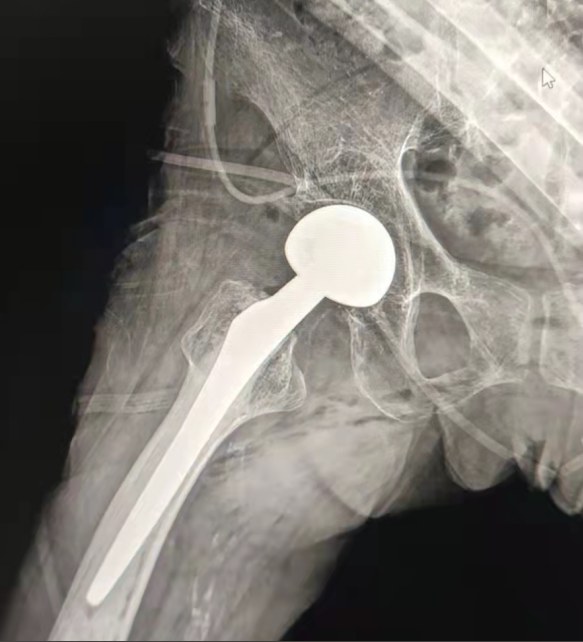

Case Sharing | 70-letni pacjent otrzymał całkowitą wymianę stawu biodrowego z cementowanym układem biodrowym Lepu

Scementowany system biodrowy:

Materiały ze stopu Co-Cr-Mo

Wysoka odporność na zużycie

Wielka wytrzymałość mechaniczna

Projekt nici na ramię

Łatwa instalacja, przytrzymanie i regulacja kąta

Polerowana obróbka powierzchniowa

Aby osiągnąć doskonałe wrastanie kości Zapewnienie stabilności wczesnej fiksacji

12/14 Standardowa konstrukcja stożka

Proximal Mix Anatomy

Distal Obie strony adge cięcia leczenia

Zmniejsz ciśnienie w jamie rdzeniowej